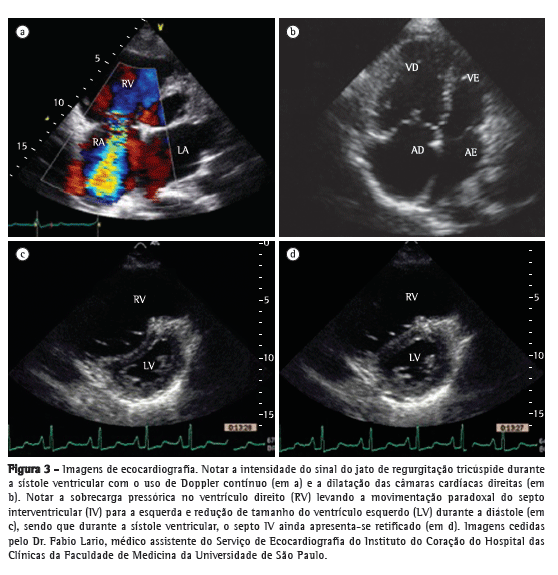

Pacientes com diagnóstico confirmado de HP apresentam alterações na radiografia de tórax em mais de 85% dos casos.(4) As principais alterações encontradas são aumento do calibre das artérias pulmonares no nível dos hilos, em 78% dos casos (Figura 1); afilamento periférico dos vasos, em 62%; e periferia pulmonar hiperlucente, em 9% (Figura 2).

O aumento do calibre das artérias pulmonares no nível dos hilos pode ser avaliado pela medida do diâmetro das artérias interlobares. O limite máximo do diâmetro transversal da artéria interlobar direita, medido de sua face lateral até a coluna de ar do brônquio intermediário, é de 16 mm em homens e de 15 mm em mulheres.(5) Devido à dificuldade de se realizar a avaliação da artéria pulmonar esquerda na incidência posteroanterior, deve-se avaliar o vaso na radiografia em perfil, partindo da transparência circular criada pelo brônquio do lobo superior esquerdo (que é visto telescopado), até a margem posterior do vaso que cavalga o brônquio; o limite máximo do normal é de 18 mm (Figura 1). O índice hilar torácico (soma da medida separada dos hilos pulmonares em relação ao diâmetro torácico total) maior do que 38% é classicamente descrito, e está presente em aproximadamente 75% dos pacientes com HP (Figura 1).(6) Raramente pode ser evidenciada a calcificação vascular, localizada geralmente no tronco da artéria pulmonar (TAP) ou em seus ramos hilares. Essa alteração é mais frequentemente relacionada a cardiopatias congênitas e embolia central crônica.

A radiografia de tórax pode auxiliar no diagnóstico diferencial com doenças do parênquima pulmonar, insuficiência cardíaca, DPOC e cifoescoliose, podendo levar a suspeita de doença tromboembólica pulmonar quando se notam áreas de oligemia, consolidações múltiplas sugestivas de infartos pulmonares ou assimetria entre as artérias pulmonares principais (Figura 2).(7)